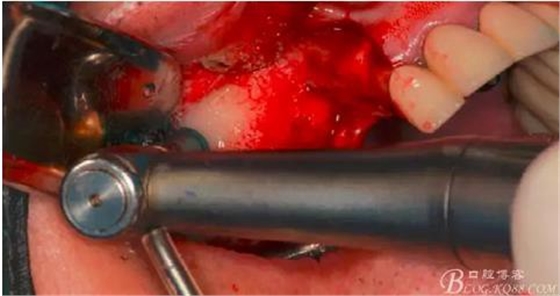

此時頰側(cè)竇膜與骨壁已經(jīng)分離,無需擔(dān)心開窗損傷竇膜。使用環(huán)切鉆以小洞口為中心開窗,轉(zhuǎn)速500轉(zhuǎn),為了保證安全,可以將種植機調(diào)成反轉(zhuǎn)模式,一樣有強大的切割效率。

因缺牙多,需要植骨的區(qū)域大,在遠中再環(huán)切一窗口。